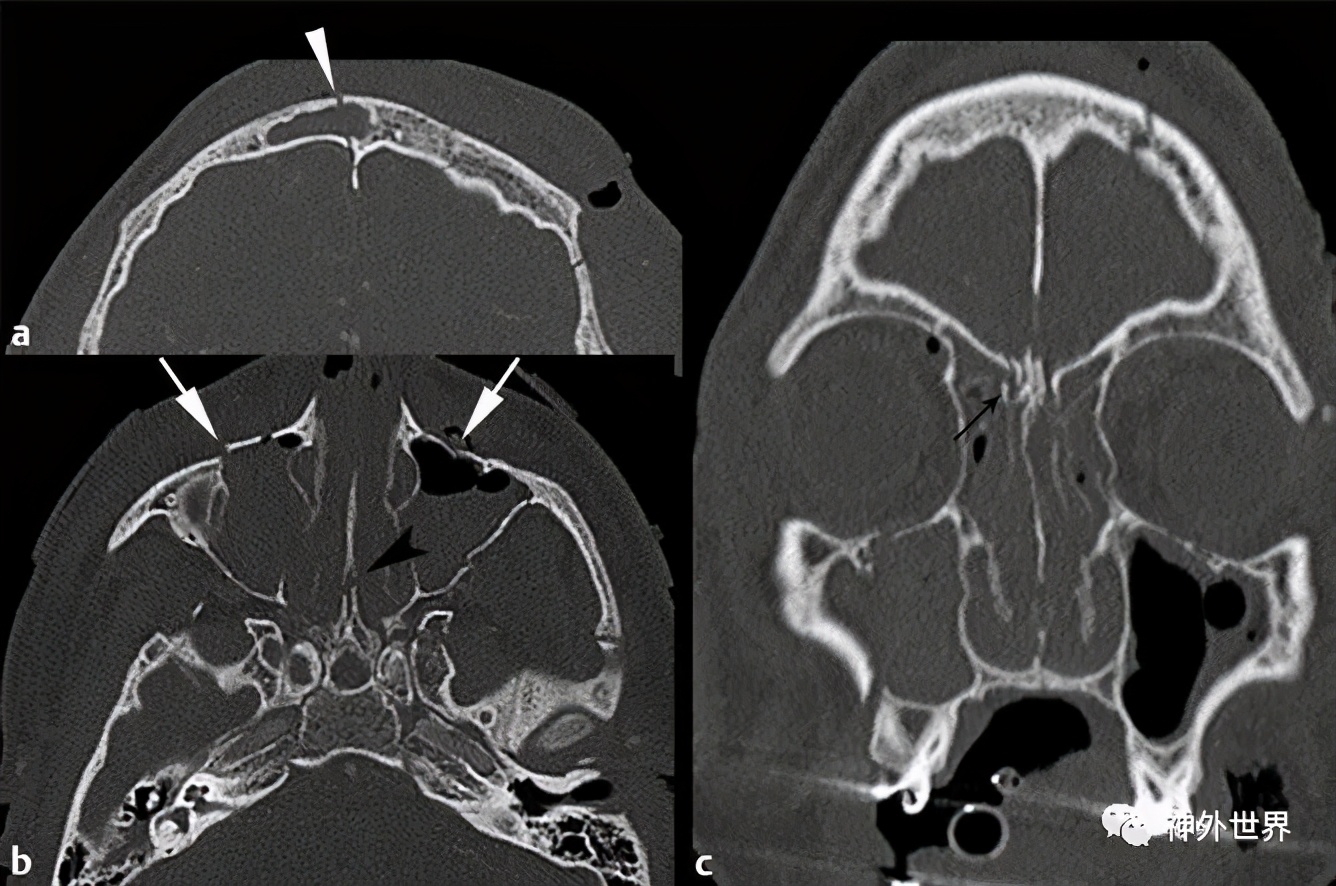

图9:复杂的前颅底骨折。 A,CT示额骨骨折,累及额窦内外面;B,累及双侧眶部(长箭头)和鼻中隔(黑箭头);C,冠状位CT示右侧筛板骨折线(黑色箭头)